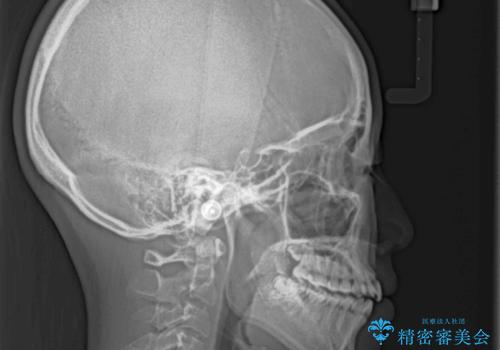

- 前歯の捻れと、ちょっとした出っ張りを気にして来院された患者様です。

歯と歯の間を削る(IPR)ことでデコボコを解消し、インビザラインで整えることとしました。

インビザライン治療特有の奥歯が接触しない時期が続き、当初予定よりも期間がかかりましたが、最終的には安定した咬み合わせと、整った前歯になりました。